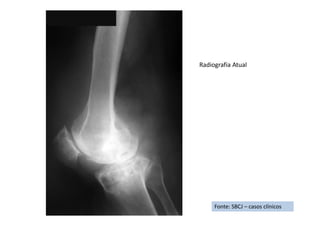

Fonte: SBCJ – casos clínicos

RX de Frente

RX de Perfil